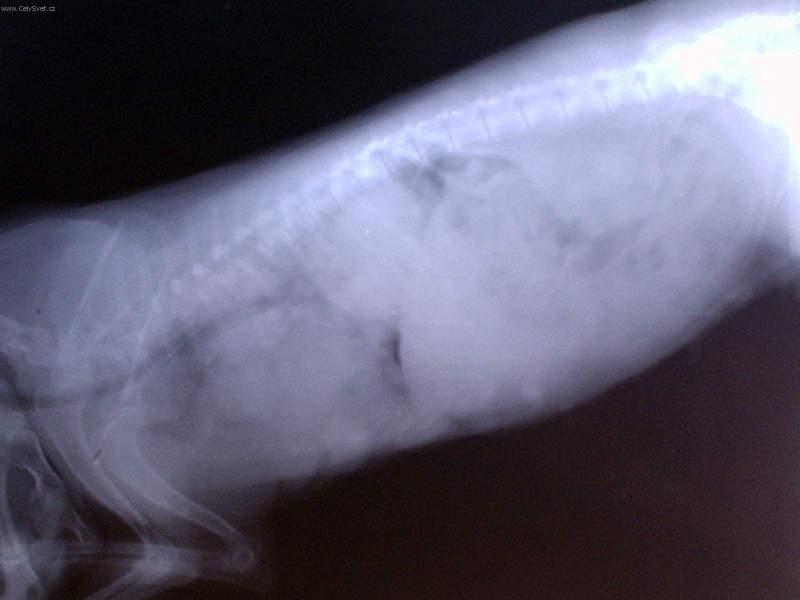

Onkologie - Novotvary mléčné žlázy u fen